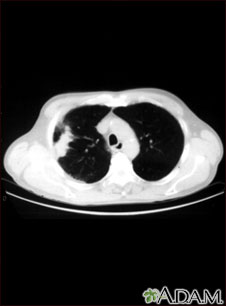

Lung with squamous cell cancer - CT scan

This CT scan shows a cross section of the lungs of a person with lung cancer. The two dark areas in the middle of the screen are the lungs. The light areas in the right lung represent the cancer (left side of picture).